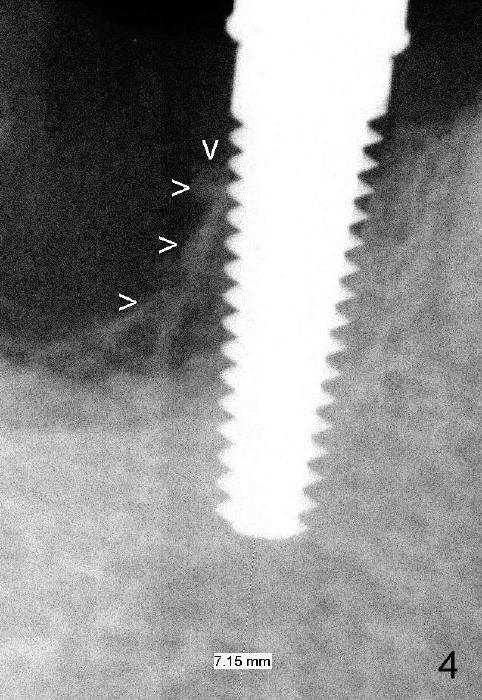

Fig.3 shows a 4.5x17 mm tap in the mesial socket (not stable). There is 7.14 mm bone between the end of the tap and the upper border of the inferior alveolar canal (red dashed line). The coronal end of the septal bone (Fig.4 >) is as high as the mesial crest.